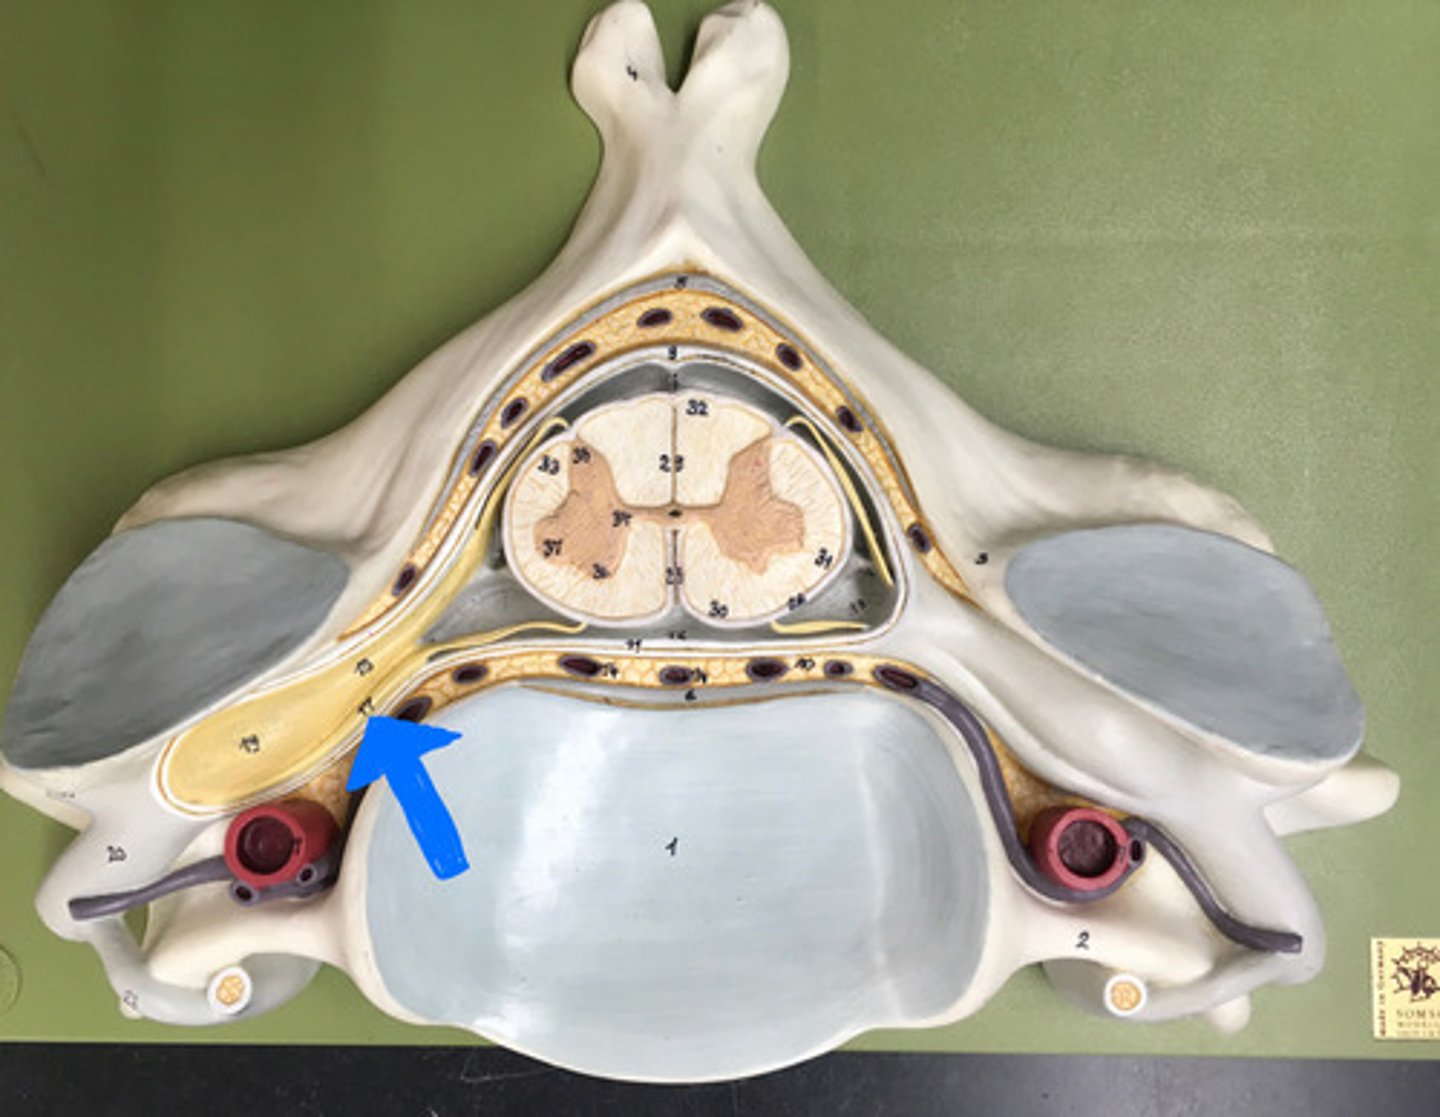

posterior median sulcus

anterior median fissure

posterior white column

anterior white column

lateral white column

posterior gray horn

anterior gray horn

lateral gray horn

gray commissure

Part of grey matter connecting the two halves of the grey matter in spinal cord

central canal

Hole in the center

Name this passageway

epidural space

dura mater

thick, outermost layer of the meninges surrounding and protecting the brain and spinal cord

subdural space

space between dura mater and arachnoid mater

arachnoid mater

middle layer of the meninges

B on model

subarachnoid space

a space in the meninges beneath the arachnoid membrane and above the pia mater that contains the cerebrospinal fluid

pia mater

the delicate innermost membrane enveloping the brain and spinal cord.

denticulate ligaments

extensions of pia mater that secure cord to dura mater laterally